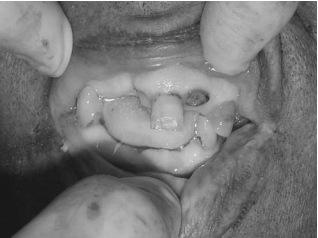

A lesão corporal observada na figura acima é melhor descrita como

Considerando a figura acima, obtida em uma necropsia de um cadáver não identificado, assinale a opção correta.